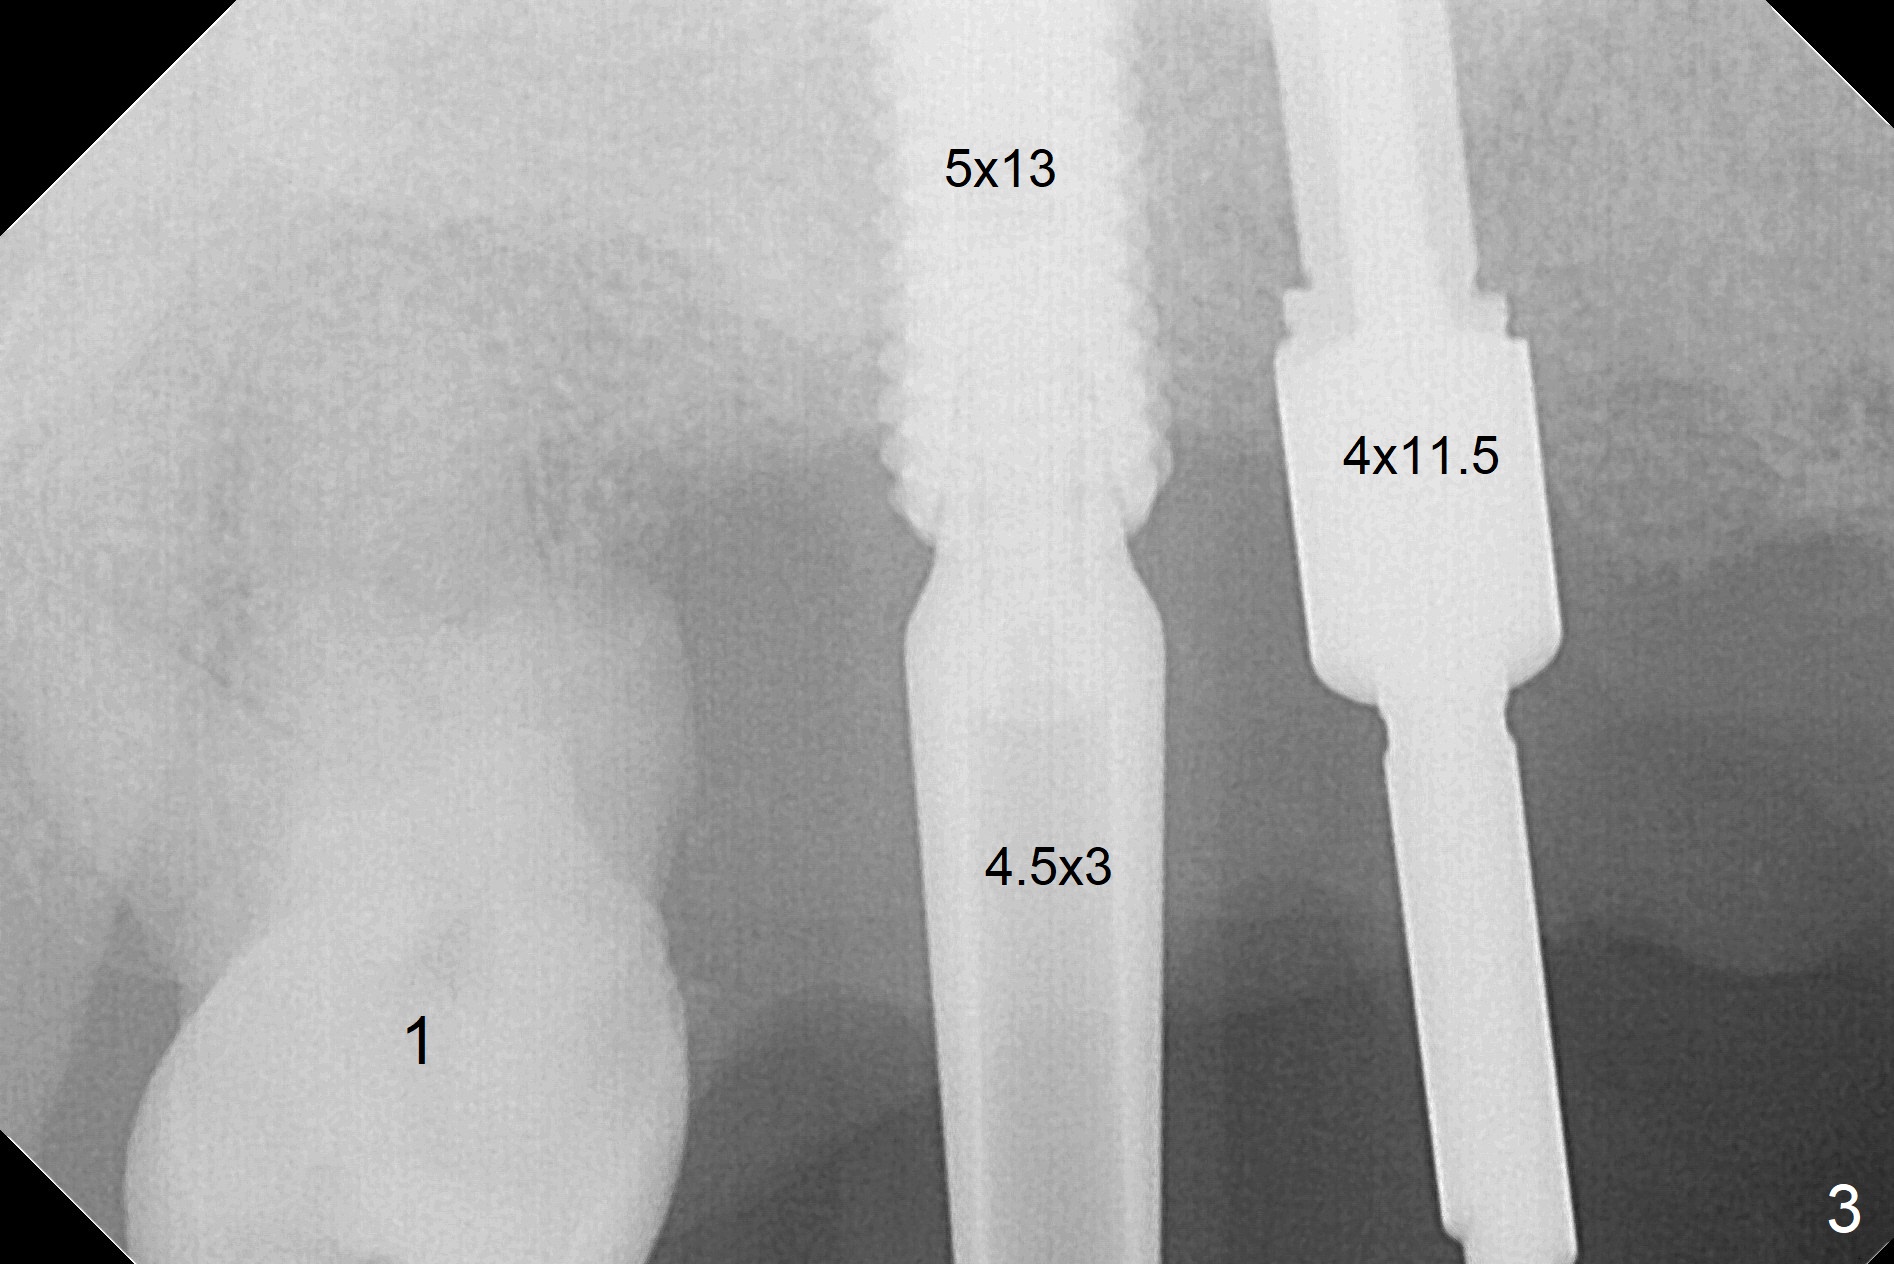

After extraction, the depths of initial osteotomy at #2, 3 and 5 are 13, 11.5 and 10 mm, respectively (Fig.1). Following adjustment of trajectory, a 3.8x13 mm UF implant is placed at #5 (Fig.2) with insertion of a 4.5x2 mm mill abutment as well as mineralized cortical/cancellous allograft (Vanilla, *). The mill abutment is chosen because the margin of a 5.5x7(5) mm cemented abutment is severely subgingival (Fig.4 at #3; ^ gingival margin). By the same token, a 4.5x3 mm mill abutment is placed at #2. In fact all of the 3 implants are placed 2-3 mm out of the bone (Fig.5). To prevent periimplantitis, abundant allograft is placed around the implants/abutments (Fig.2,4 *). Nearly 2 months postop, the mill abutment at #2 is adjusted for its height, while a 5.5x2.5 mm mill abutment is placed at #3 (Fig.6). To regain the buccal gingiva, the buccal margin of the provisional is shortened (Fig.6,7). Two weeks later, the gingival regrowth is not obvious (Fig.8 (nearly 3 months postop)). Local poor oral hygiene remains. A provisional FPD is fabricated. If his occlusion is normal for another 2 weeks, impression will be taken for upper (or UL) permanent restoration.